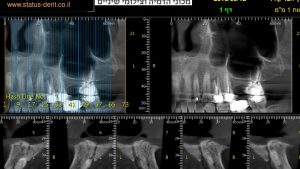

A 69 year old patient needed a sinus lift and several implants.

In April 2018 he got his first DIVA implant at area 16 and in June another DIVA implant was implanted at area 27.

By using the DIVA implants, Dr. Ben-Zion Marcovich prevented an open sinus lift.